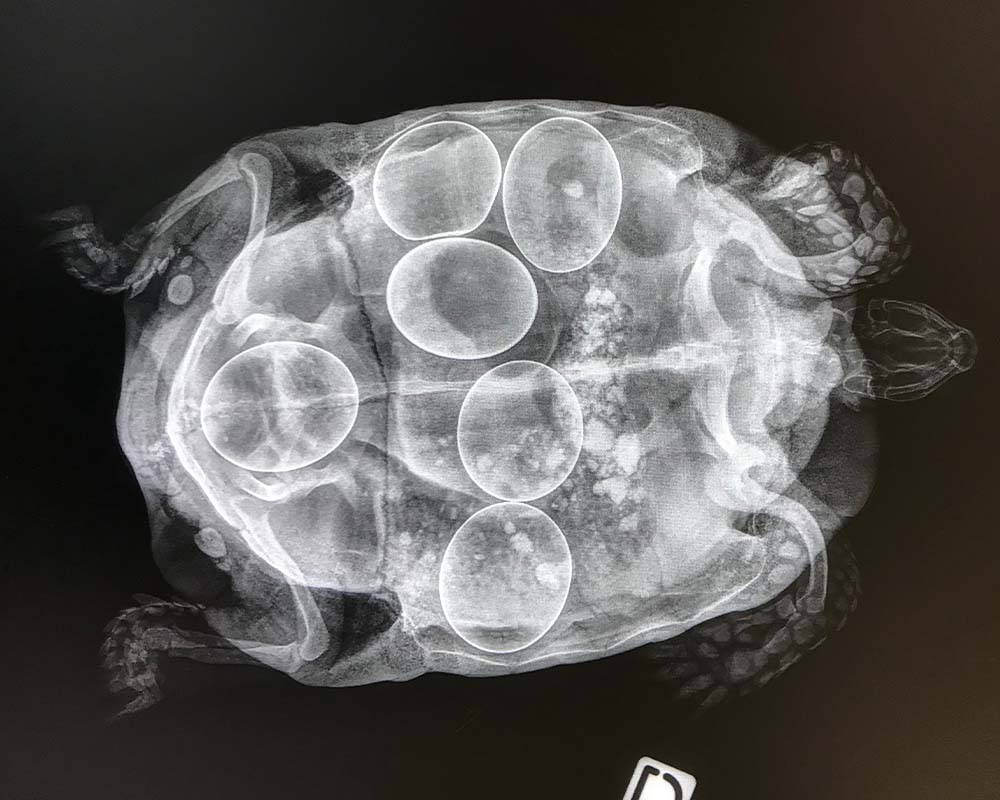

Consultation NAC (Nouveaux Animaux de Compagnie)

Les Nouveaux Animaux de Compagnie ont des besoins bien spécifiques. Nous possédons le matériel adapté aux soins des lapins, furets, rongeurs et tortues.

Nous vous proposons des consultations de médecine préventive et générale ainsi que des interventions chirurgicales (coupe de dents, stérilisation, abcès…)